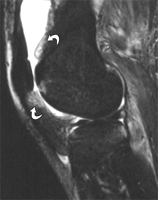

I) Signes d'Arthrite septique aigue à l'IRM :

- prise de contraste synoviale (98%),

- oedème péri-synovial (84%),

- épanchement articulaire (70%),

- diverticule synovial (53%),

- prise de contraste de l'épanchement (30%),

- épaississement synovial (22%)